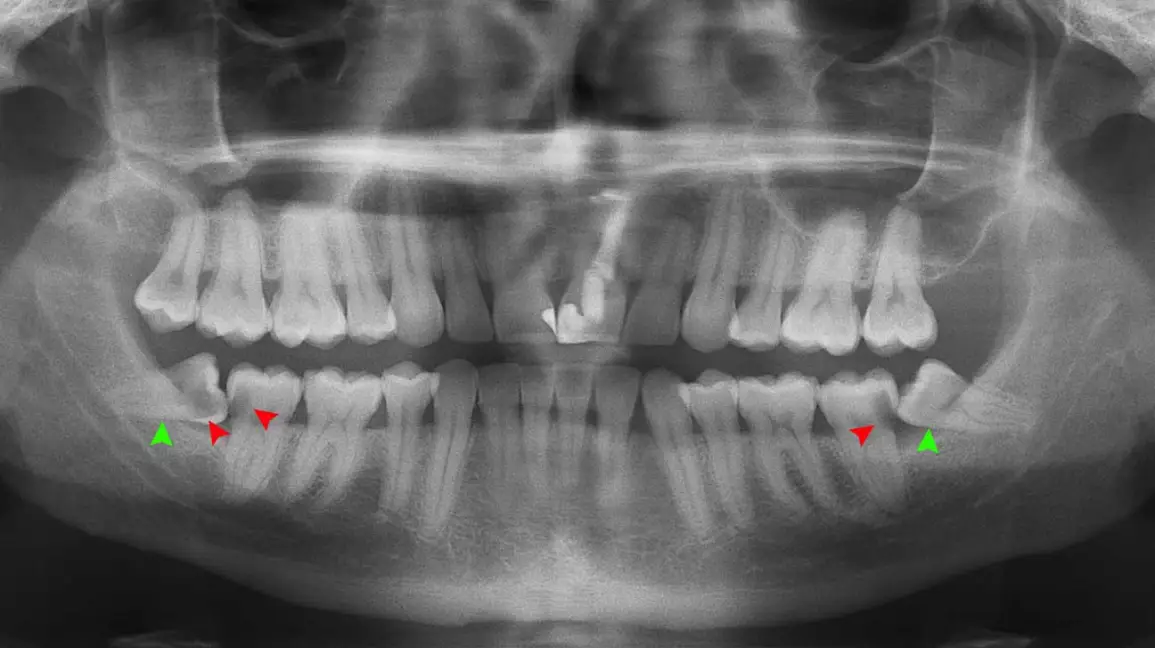

매복 사랑니 발치

매복 사랑니가 위험한 이유

비정상 각도·방향 → 옆 어금니 손상·충치

잇몸 염증·심한 통증 → 부기·발열·개구 장애

신경관 근접 → 방치 시 감각 이상 위험

매복 사랑니 발치, 왜 플란트구강악안면외과 치과일까요?

1. 10,000건 이상의 압도적인 임상 경험

저희 치과의 의료진은 대학병원에서의 풍부한 경험을 바탕으로 10,000건 이상의 사랑니 발치 케이스를 성공적으로 진행했습니다.

3. 신경 손상 최소화를 위한 정밀 진단 및 계획

3D CT를 활용한 정밀 진단: 발치 부위의 뼈 구조, 사랑니 뿌리의 형태, 신경관과의 거리 및 위치 등을 3차원적으로 정확하게 파악하여 신경 손상 가능성을 미리 예측하고 대비합니다.

개별 맞춤 발치 계획 수립: 정밀 진단 결과를 바탕으로 각 환자분의 케이스에 최적화된 발치 계획을 수립하고, 신경관의 위치를 고려한 안전한 각도와 방법으로 시술을 진행합니다.

숙련된 의료진의 섬세한 시술: 다년간의 경험과 숙련된 기술로 신경 구조물을 피해 안전하게 사랑니를 분리하고 발치합니다.